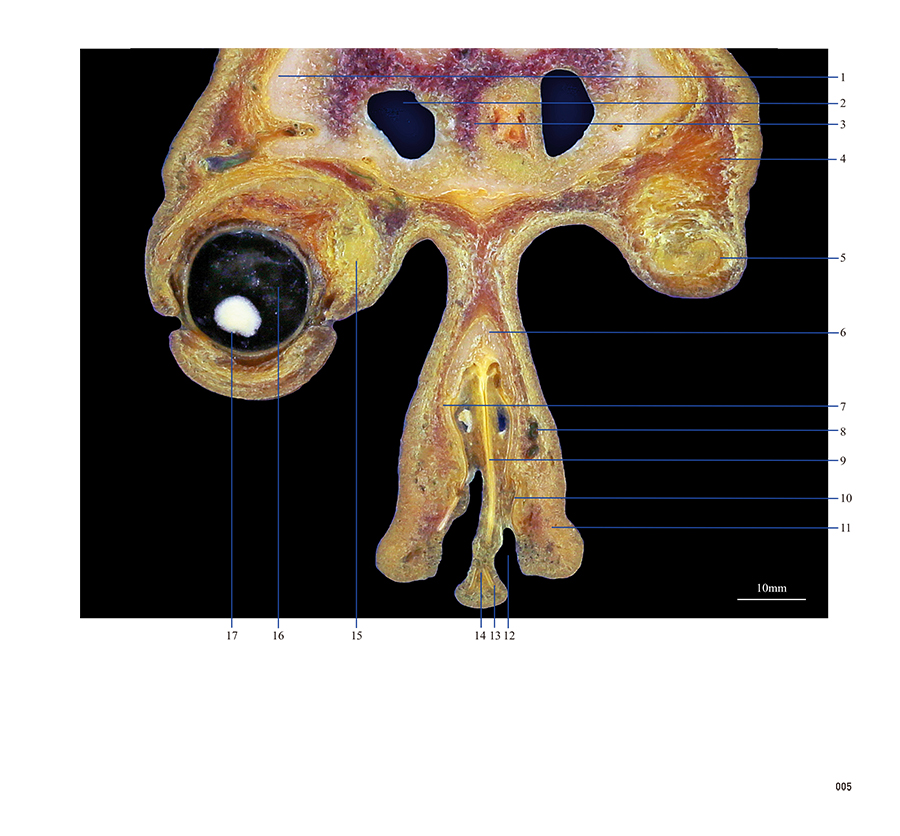

本书从数据集每隔1.2mm选取一幅图像,截取眼、耳、鼻及毗邻颅底的局部区域图像,共112幅图像。同时配以相应部位的CT图像对照。本书特色是断层解剖图利用数字图像处理技术优势,放大并清晰展示眼、耳、鼻及毗邻颅底断面的局部区域结构,组织色泽真实,甚至能够清晰显示肌肉纹理、筋膜纹路等细节结构,图像质量高于美国《人体断层解剖学彩色图谱》(引进版)类似图谱图像质量。对眼科、耳鼻咽喉科和神经内外科医生理解相关解剖结构有较大帮助。